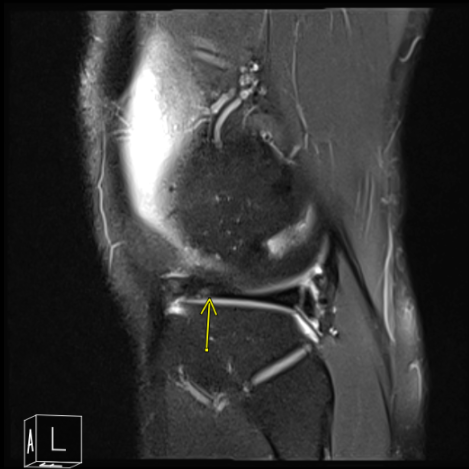

MRI of his right knee was presented and clearly showed that there is tearing of the lateral meniscus anterior horn with parameniscal cyst tracking into the anterior intercondylar notch adjacent to the anterior root attachment site measuring 2 x 2.3 x 0.8 cm. Trace right knee joint effusion.

MRI of the right knee